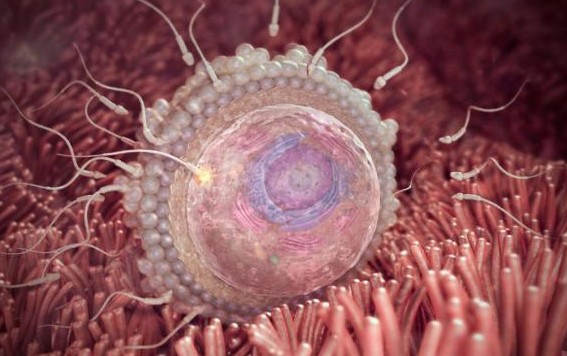

في البداية وقبل أي شيء حتى يحدث الحمل لابد من أن يتم التلاقي ما بين حيوان منوي وبويضة حتى تحدث عملية التلقيح، ولا يمكن اعتبار أول أسبوعين يتم احتسابهم من الحمل هم فترة تكوين فعلية للجنين لأنه ذه الفترة التي تتوقف بها الدورة الشهرية وذلك بعد أخر دورة شهرية حدثت للمرأة.

خلال هذه الفترة وهي الأسبوعين الأول الثاني بعد نهاية أخر دورة شهرية لدى المرأة تبدأ عملية التخصيب من خلال الحيوان المنوي للبويضة ولكن يقوم الطبيب الخاص بك باحتساب هذه الفترة ضمن فترة الحمل الخاص بك وفيما يلي شرح تفصيلي لمراحل نمو الجنين بالصور للتعرف عليها بشكل واضح.

خلال هذا الأسبوع تخرج البويضة من المبيض متجهة إلى قانوة فالوب حيث تلتقي هناك بالحيوان المنوي وتكون جاهزة للتحول لبويضة مخصبة في فترة تتراوح من 12 وحتى 24 ساعة، إذا لم يحدث جماع خلال هذه الفترة الزمنية تموت البويضة ولكن عند الجماع تتحرك الحيوانات المنوية بسرعة كبيرة وتخصب البويضة.

بعد أن يتم تخصيب البويضة تعمل بشكل تلقائي على إغلاق غشائها حتى لا يدخل إليها أي حيوان منوي آخر ويتم الإتحاد ما بين الحيوان والمنوي والبويضة وتبدأ خلال هذه الفترة تكوين مجموعة من الكروموسومات التي تساهم بدورها في تحديد نوع الجنين وصفاته وغيرها.

بعد ذلك تذهب البويضة إلى الرحم ويحدث لها مجموعة من الانقسامات وتصبح مشابهة لثمرة التوت.